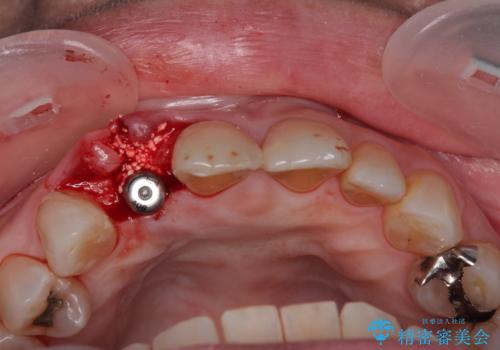

仮歯を事前に用意し、インプラント埋入時に即日で仮歯を装着する、即時荷重インプラントの計画で治療を進めて行くこととしました。

新幹線や飛行機を利用しても来院であり、極力来院回数を減らしたり、東京に用事があるタイミングに合わせてアポイントを調整したりと、負担が少なくなるようにして治療を進めて行きました。

来院間隔があいたため、予定よりも長くなりましたが、大きなトラブルもなく、外科処置は1回のみ、最小の来院数で無事に治療を終えることができました。